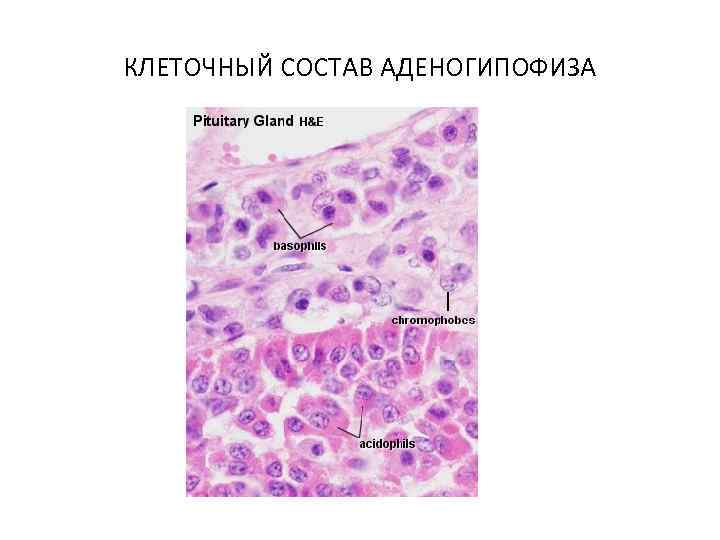

КЛЕТОЧНЫЙ СОСТАВ АДЕНОГИПОФИЗА

КЛЕТОЧНЫЙ СОСТАВ АДЕНОГИПОФИЗА

ГОРМОНЫ АДЕНОГИПОФИЗА Образует гормоны, стимулирующие активность периферических желез (тропные гормоны). 1. ТТГ – тиреотропный гормон - активация щитовидной железы 2. АКТГ – адренокортикотропный гормон активация коры надпочечников 3. ГТГ – гонадотропные гормоны - активация половых желез

ГОРМОНЫ АДЕНОГИПОФИЗА Образует гормоны, стимулирующие активность периферических желез (тропные гормоны). 1. ТТГ – тиреотропный гормон - активация щитовидной железы 2. АКТГ – адренокортикотропный гормон активация коры надпочечников 3. ГТГ – гонадотропные гормоны - активация половых желез